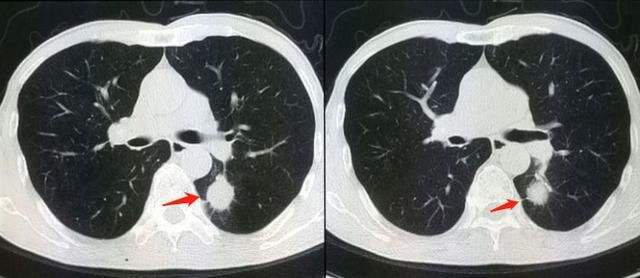

16层螺旋ct多种重建方法在诊断肋软骨骨折中的应用 罕见病 疑难病 会诊平台 专家会诊 网上会诊 医学影像

128层螺旋ct三维重建在胸部外伤肋骨及肋软骨骨折诊断中的应用 中国期刊网

多层螺旋ct后处理重建在肋骨和肋软骨骨折诊断中的临床应用 中国期刊网

医院动态 放射科利用多层螺旋ct后处理重建技术诊断肋软骨骨折 药最网 Www Yaozui Com

16层螺旋ct多种重建方法在诊断肋软骨骨折中的应用 罕见病 疑难病 会诊平台 专家会诊 网上会诊 医学影像

16层螺旋ct多种重建方法在诊断肋软骨骨折中的应用 罕见病 疑难病 会诊平台 专家会诊 网上会诊 医学影像